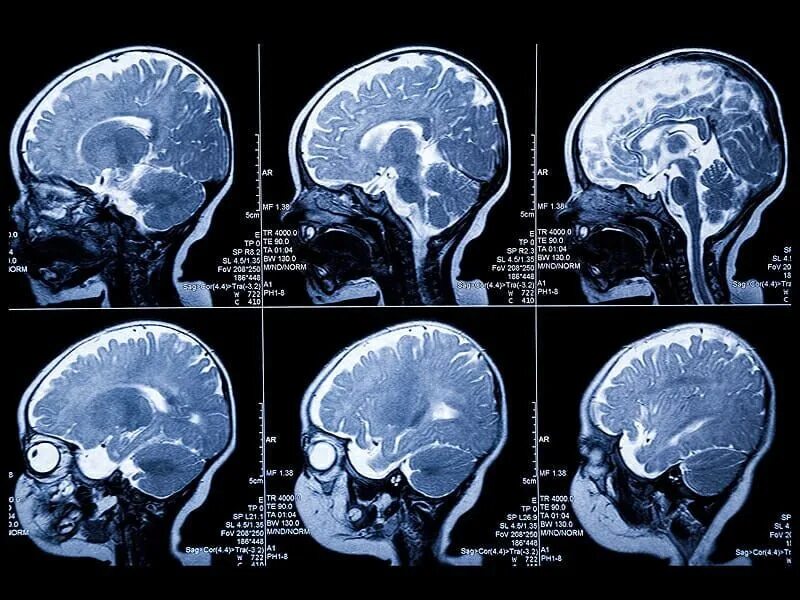

Кт с какого возраста можно делать ребенку